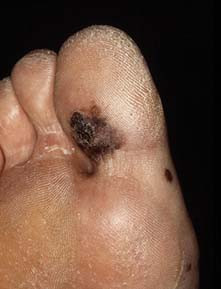

Een huisarts in een normpraktijk ziet éénmaal in de 2-3 jaar een nieuwe patiënt met een melanoom. Intermitterende excessieve zonblootstelling (verbranding) is de belangrijkste risicofactor, met name bij een licht huidtype. Bij circa 10% van de melanomen is sprake van een familiair…